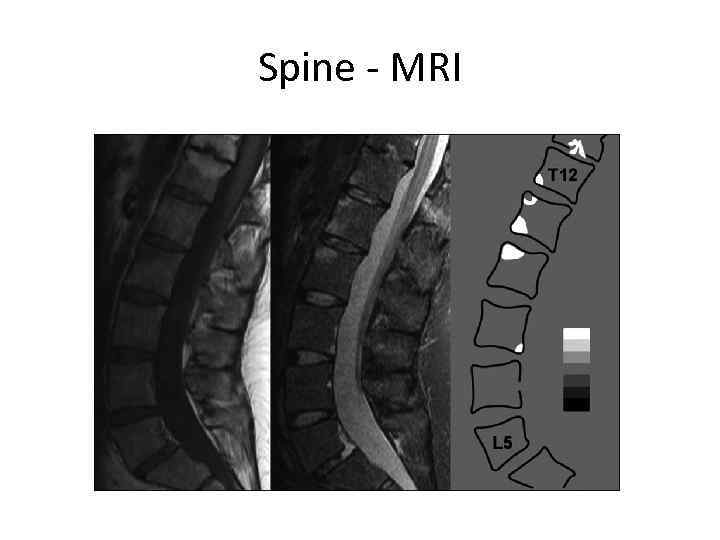

Spine - MRI